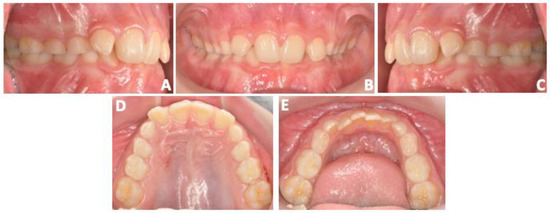

3.1. Clinical Outcomes